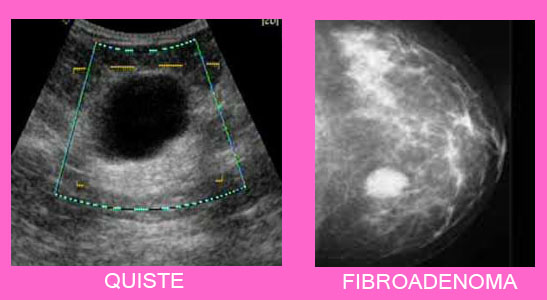

Tumores benignos y malignos de mama 😈

Tumores benignos de la mama Salud al día 😈